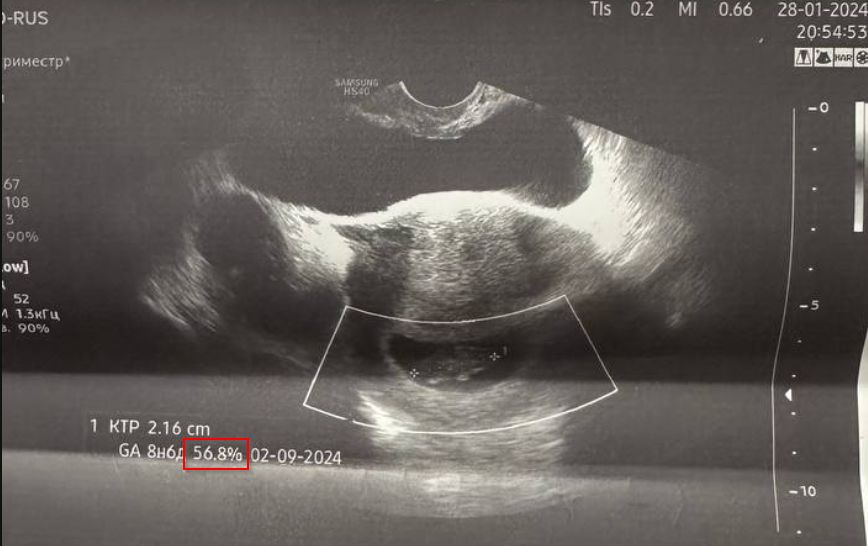

Что значит этот % на узи?

УЗИ, КТГ, доплерВсё изучаю и кручу в руках узи, наткнулась на новый для меня показатель.

Что значит этот %? На снимках обвела красным.

Скорее всего процентиль для этого срока. От 10 до 90 это хорошо